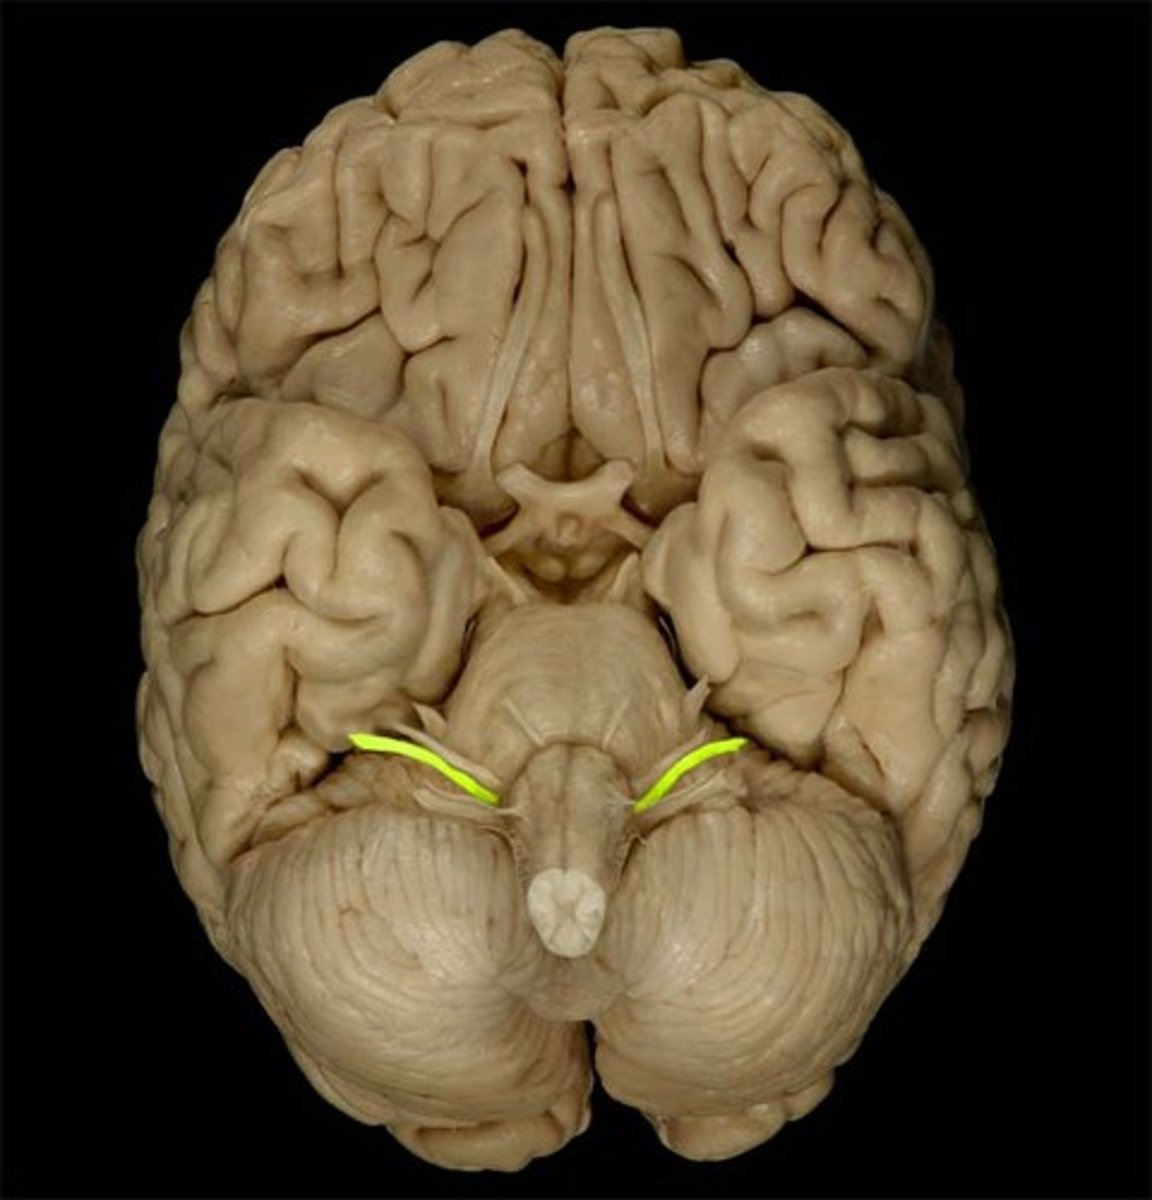

optic nerve (CN II)

Sensory cranial nerve related to vision

optic chiasm

point at which optic nerve fibers cross in the brain

optic tracts

the continuation of the optic nerve fibers beyond the optic chiasma

primary visual cortex

•Located within occipital lobe; receives, processes, stores visual information